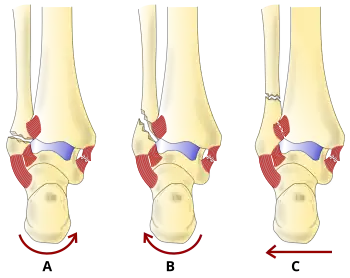

There are several classification schemes for ankle fractures. Out of the following, the Lauge-Hansen and Danis-Weber classification systems are most commonly used.[9]

- The Lauge-Hansen classification categorizes fractures based on the mechanism of the injury as it relates to the position of the foot and the deforming force (the most common type is supination-external rotation)

- The Danis-Weber classification categorizes ankle fractures by the level of the fracture of the distal fibula (type A = below the syndesmotic ligament, type B = at its level, type C = above the ligament), with use in assessing injury to the syndesmosis and the interosseous membrane